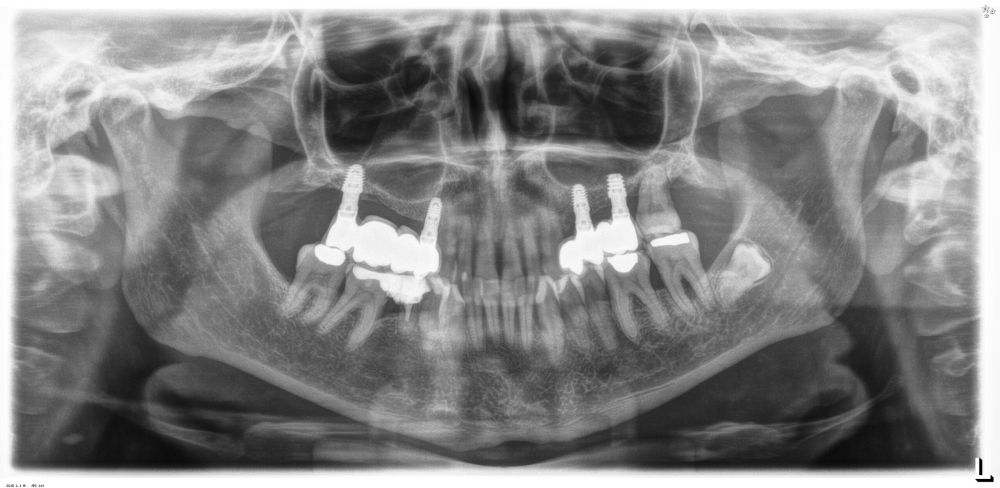

Como primer paso, se realiza un escaneado intraoral de la paciente, para poder generar un encerado virtual con las piezas que queremos rehabilitar con implantes (Figuras 6-8). Esto nos permite planificar con claridad el caso y desde el modelo tridimensional, generar los provisionales y las guías quirúrgicas basadas en la posición protésica, que desde el flujo digital pueden imprimirse (Figuras 9-14). Desde el encerado podemos además generar otras guías, en este caso radiológicas, con las que realizar el Cone-Beam Computed Tomography (CBCT) de planificación. Con esta información tenemos en el mismo estudio radiológico la fusión de nuestra planificación quirúrgica y la posición real de la prótesis adaptada a la oclusión, muy útil para generar una planificación que contempla todos los parámetros. En este caso, se planifican implantes cortos de 6,5 mm en el primer cuadrante, de morfología Core-Xâ, para lograr una correcta estabilidad primaria en un tipo óseo IV como vemos en el corte seccional (Figuras 15 y 16). En el segundo cuadrante, con similares características, planificamos implantes de 6,5 y 5,5 mm de longitud (Figuras 17 y 18).

Transcurridos 6 meses desde la carga inicial progresiva, se puede elaborar la prótesis definitiva, trasladando los parámetros de la prótesis provisional (Figura 27). La paciente continúa en seguimiento durante un año, realizándose radiografías de control para el monitoreo del hueso crestal, sin encontrarse pérdida ósea asociada en ninguno de los implantes (Figuras 28-29).